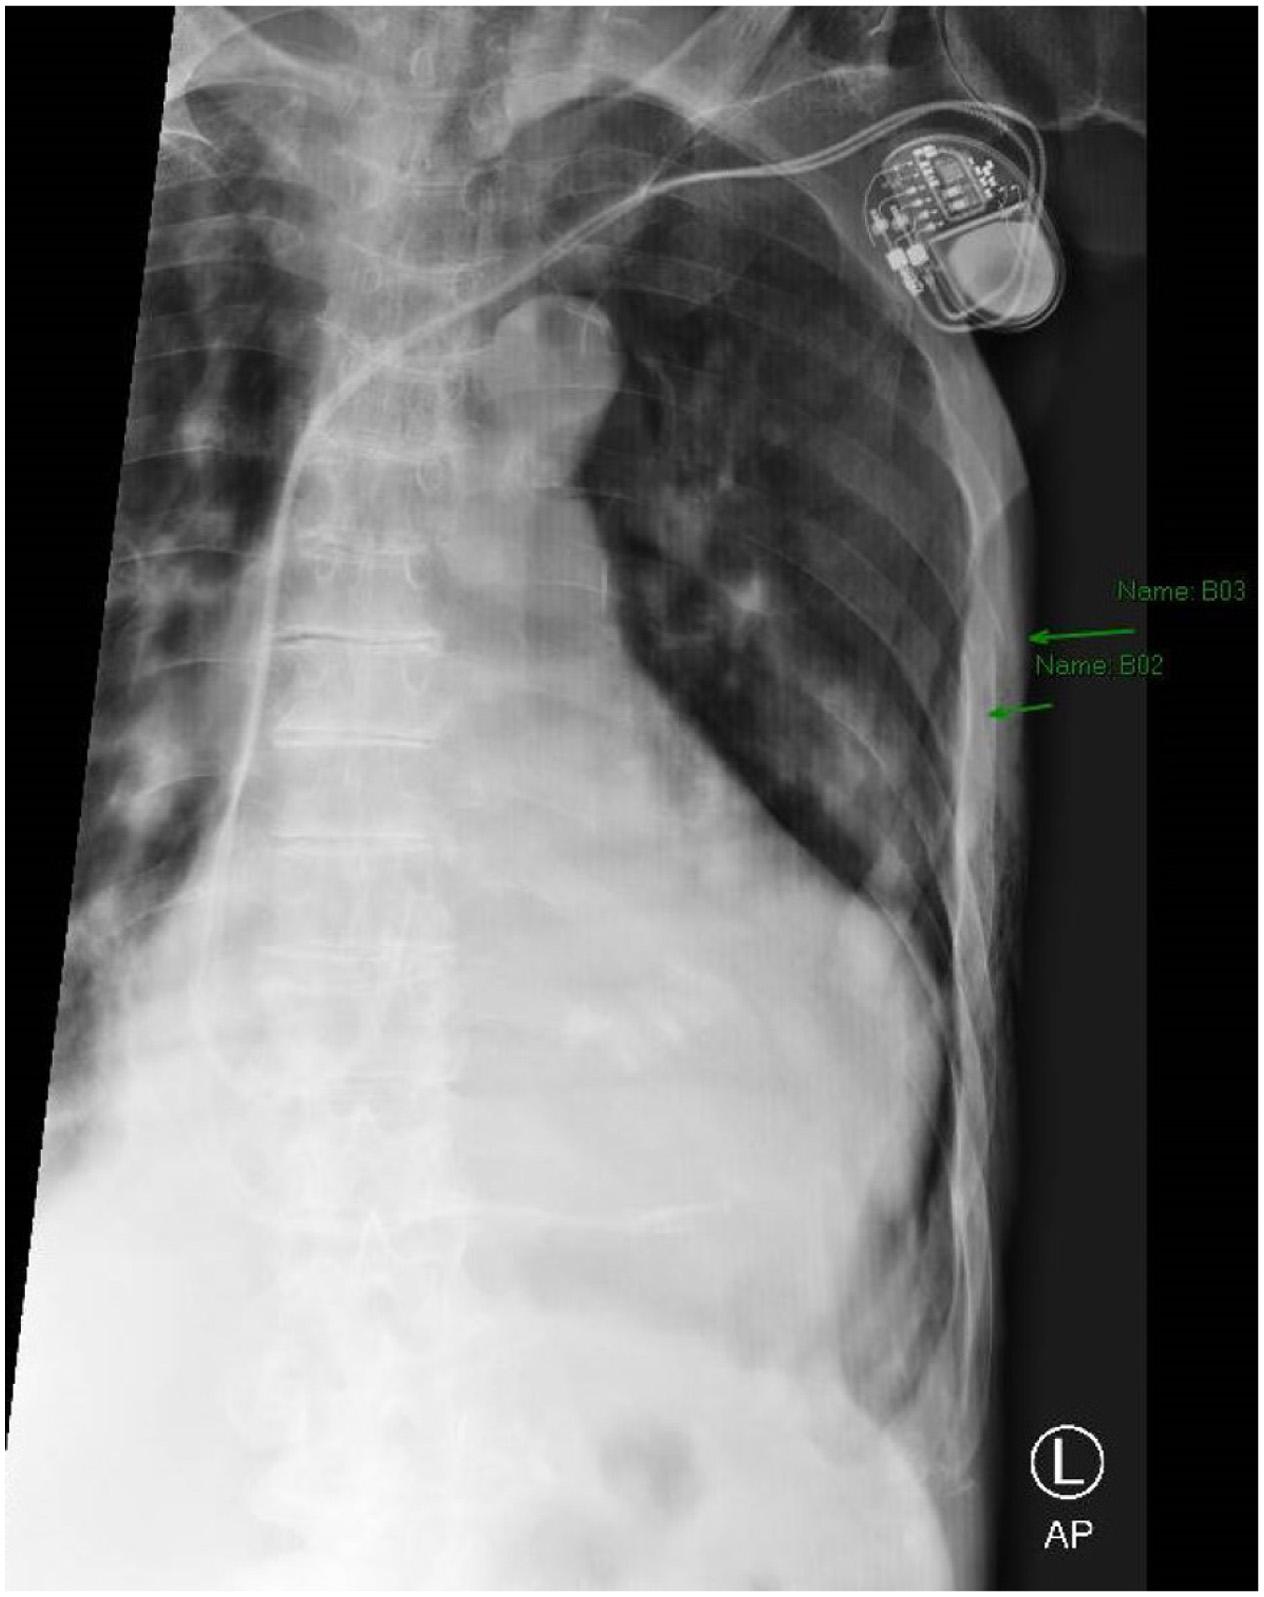

Thepatientwasplacedon100%oxygenvianonrebreathermaskandtransportedtoalocalemergency department(ED).UponarrivalattheEDhedeniednew complaints,andhisvitalsandphysicalexamwerenot significantlychanged.Hiselectrocardiogram(ECG)showed anatrialsensedpacedrhythmconsistentwithpriorECGs. Hehadachestradiograph(CXR)showingleft fifthandsixth ribfractureswithamoderatecircumferentialpneumothorax (Images2 and 3).

Image2. Chestradiographwitharrowspointingtoleft-sidedmoderatecircumferentialpneumothorax.Thereisalossofsymmetry,avisible lungborder,andlossoflungmarkingsuperiortothelungborder.

Image3. Magnifiedviewofthechestradiographdemonstrating fracturesofribs fiveandsix(arrows).